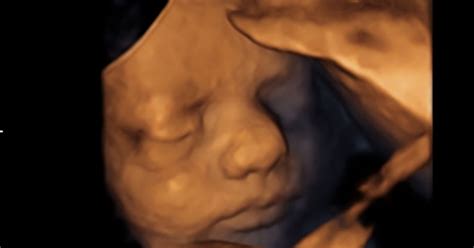

Razvoj ploda skozi trimesesečja

Nosečnost traja v povprečju 40 tednov in je običajno razdeljena na tri trimesesečja, vsako s svojimi specifičnimi spremembami tako pri materi kot pri plodu.

- Prvo trimesesečje (teden 1-13): V tem ključnem obdobju se položijo temelji za razvoj vseh organov in telesnih sistemov. Zarodek se hitro razvija, iz majhne celice postane prepoznaven človek. Materino telo doživlja obsežne hormonske spremembe, ki lahko povzročijo utrujenost, slabost in druge simptome. V tem času je še posebej pomembno skrbeti za zdravo prehrano, izogibati se škodljivim snovem in se posvetovati z zdravnikom o vseh vprašanjih.

- Drugo trimesesečje (teden 14-27): Mnoge ženske v tem obdobju občutijo olajšanje od jutranje slabosti, energija se poveča, telo pa se postopoma prilagaja rasti ploda. Plod hitro raste, kosti se utrjujejo, začne se razvijati sluh in vid. Materin trebuh postaja opazno večji, kar lahko povzroči nove telesne občutke, kot so bolečine v hrbtu ali otekanje nog. To je tudi čas, ko se lahko začnejo čutiti prvi gibi otroka.

- Tretje trimesesečje (teden 28-40): V zadnjem trimesesečju plod pridobiva težo in moč, pripravlja se na rojstvo. Materino telo se še naprej spreminja, pritisk na mehur se povečuje, lahko se pojavijo popadki Braxton-Hicksa. Ženska se začne fizično in psihično pripravljati na porod. Pogosti so obiski pri ginekologu, ki spremlja stanje matere in otroka ter pripravlja načrt poroda.